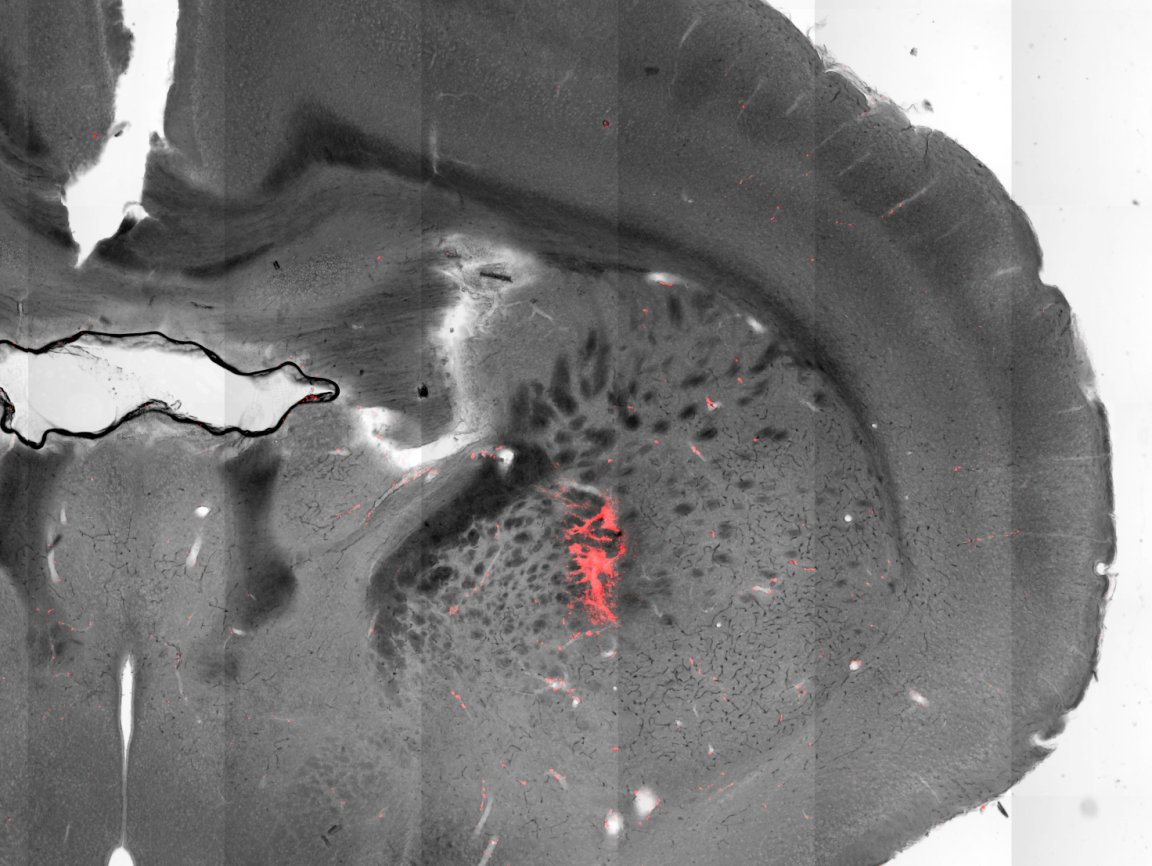

These results were achieved working with mice that had been genetically engineered such that targeted neurons would produce ion channels sensitive and even receptive to temperature. Nanoparticles consisting of a cobalt-ferrite core coated in manganese ferrite were injected into the brain, attaching themselves to neurons.

Applying an alternating magnetosphere causes the magnetization of these nanoparticles to switch back and forth, raising their temperature. As a result, the ion channels open up, causing the associated neurons to fire.